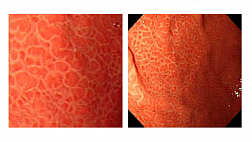

В просвете желудка вязкий секрет, плохо отмывается от стенок. Слизистая в теле отечна, с умеренной гиперемией. В антральном отделе гипертрофированные складки на верхушках эрозированные очаги с признаками эпителизации. Складки во всех отделах желудка при инсуффляции расправляются полностью, в дистальных отделах отсутвуют коллекторные венулы. Перистальтика симметричная. Привратник овальной формы, не смыкается . Дуоденогастральный рефлюкса нет .В инверсии кардия охватывает аппарат в виде "купола".

12-кишка: Просвет луковицы двенадцатиперстной кишки обычный, содержит небольшое количество желчи, перистальтика активная , слизистая оболочка розового цвета, ворсинки сохранены. Так же прослеживаются пигментированные образования от 2мм до 8мм. серо-синюшного оттенка. Постбульбарном отделе множественные пигментые образования до 10мм, единичные кратообразные пигментные образования до 15мм, глубиной до 5мм., дно покрыто серым фибрином. Биопсия 2-а кусочка.

Заключение: ГПОД. Грыжевая гастропатия. Эрозивная гастропатия антрального отдела желудка. MTS Меланома ЛДПК, залуковичного отдела. Биопсия.